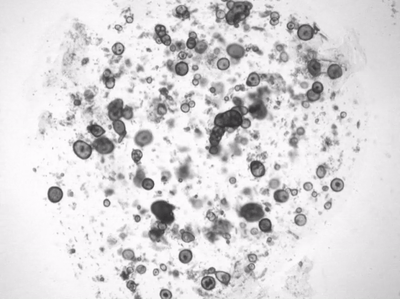

据外媒CNET报道,会“流泪”的无体人类泪腺听起来像是科幻电影里的东西。但来自Hubrecht研究所和UMC Utrecht的研究人员利用干细胞在培养皿中生长出微小的泪腺,以模仿真实的东西。他们希望这些所谓的有机体可以作为研究人类泪腺细胞如何产生眼泪的模型。他们的最终目标是:更好地理解和治疗干眼症或自身免疫性疾病干燥综合征以及泪腺癌症等疾病。

有机体是在体外以3D悬浮液的形式,从少量干细胞最终繁殖形成类似真实器官的东西,如小脑、膀胱,或在本例中,位于上眼睑内的腺体。

泪腺是由几种细胞组成的。荷兰研究人员培育的实验室生长的腺体只由一种类型组成,并在化学刺激下“哭泣”,如去甲肾上腺素,一种神经递质,从我们的神经元向我们的泪腺发出信息。